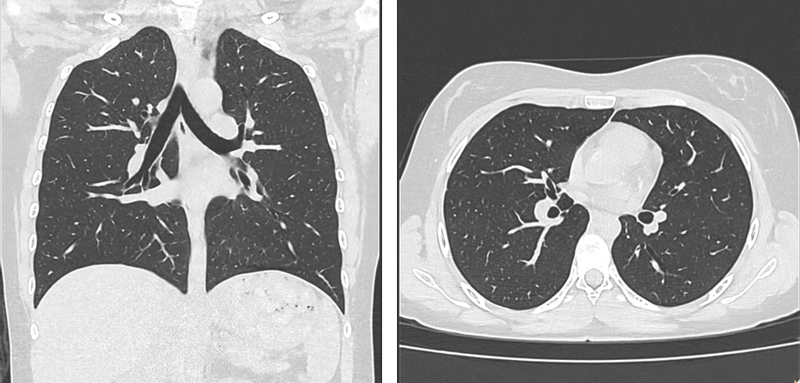

Um eine möglichst frühe Erkennung bei gleichzeitig niedriger Strahlendosis zu gewährleisten, ist es erforderlich, die Bildqualität auch bei Low-Dose-Protokollen aufrechtzuerhalten.

Lungenstrukturen sind komplex, und kleinste Rundherde (<5 mm) müssen zuverlässig detektiert und eingeordnet werden. Atembewegungen, variierende Lungenfüllung und anatomische Überlagerungen können zu Artefakten führen, die die Diagnose erschweren oder zu unnötigen Folgeuntersuchungen führen.

Durch unsere KI-gestützten Technologien werden Bilder erzeugt, die auch bei sehr niedriger Dosis eine hohe diagnostische Aussagekraft bieten – ohne zusätzliche Hardwareanforderungen.

Die Herausforderung der feinen Läsionsdarstellung wird durch Precise Image adressiert, das Bildrauschen reduziert und die Klarheit verbessert.